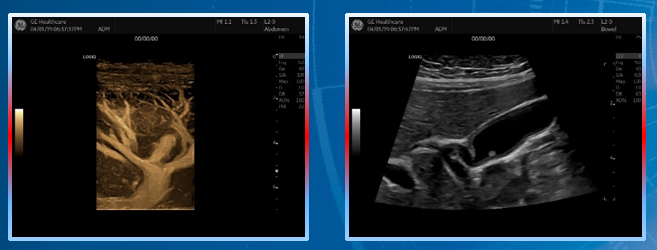

冰晶探头技术带来高穿透力——兼顾穿透及分辨。

超宽频宽相应,频带:2-10MHz——兼容血管、小器官、腹部、小儿全身应用。

支持B-Flow灰阶血流成像及MVI超微细血流成像。

支持双模态弹性成像、双模态超声造影、容积导航。

穿透力与分辨力的完美体现